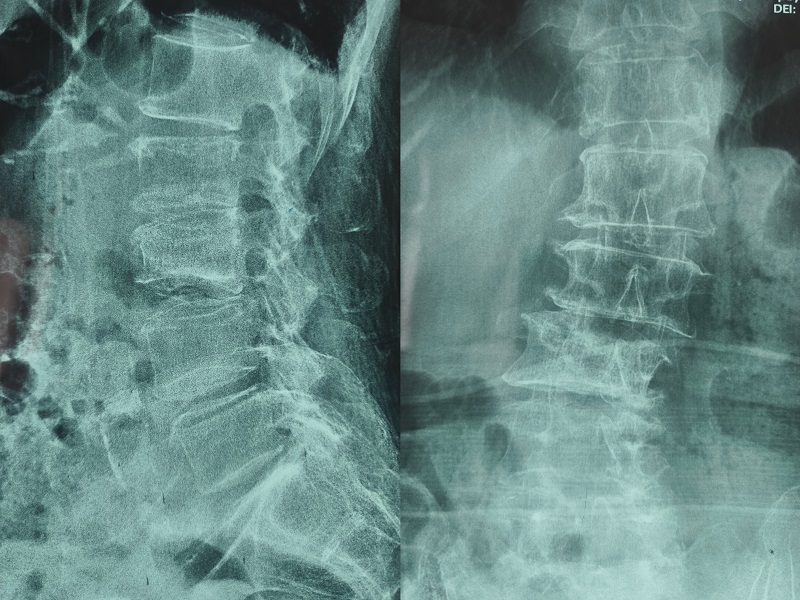

术前诊断:腰椎侧弯、陈旧性腰椎压缩性骨折(L2L3)、重度骨质疏松

术前图像